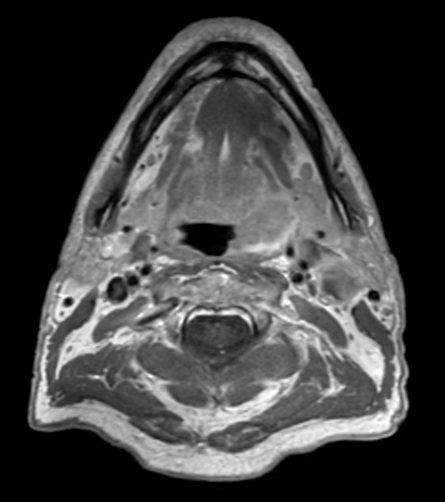

A 75-year-old male with oropharynx squamous cell carcinoma in the left tonsil region with extension into the soft palate, caudal border lower tonsil region, no midline crossing. On the left side in the neck there are also three enlared lymph nodes on level 2 and 3 with central necrosis and signs of limited extracapsular extensionn, T2N2b. Patient underwent MRI simulation in the radiotherapy (5-point) positioning mask in Ingenia MR-RT 3.0T using the Flex coils in combination with integrated Posterior FlexCoverage coil.

T1w TSE mDIXON (water only) pre contrast